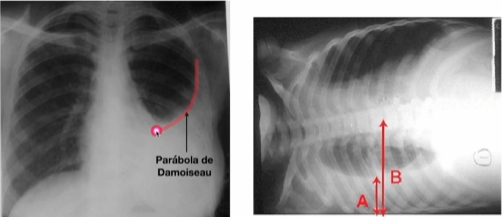

Qual o aspecto do Rx de tórax no derrame pleural?

A

NB: em decúbito, há corrimento do líquido, fazendo o aspecto de redução da parte preta (A)